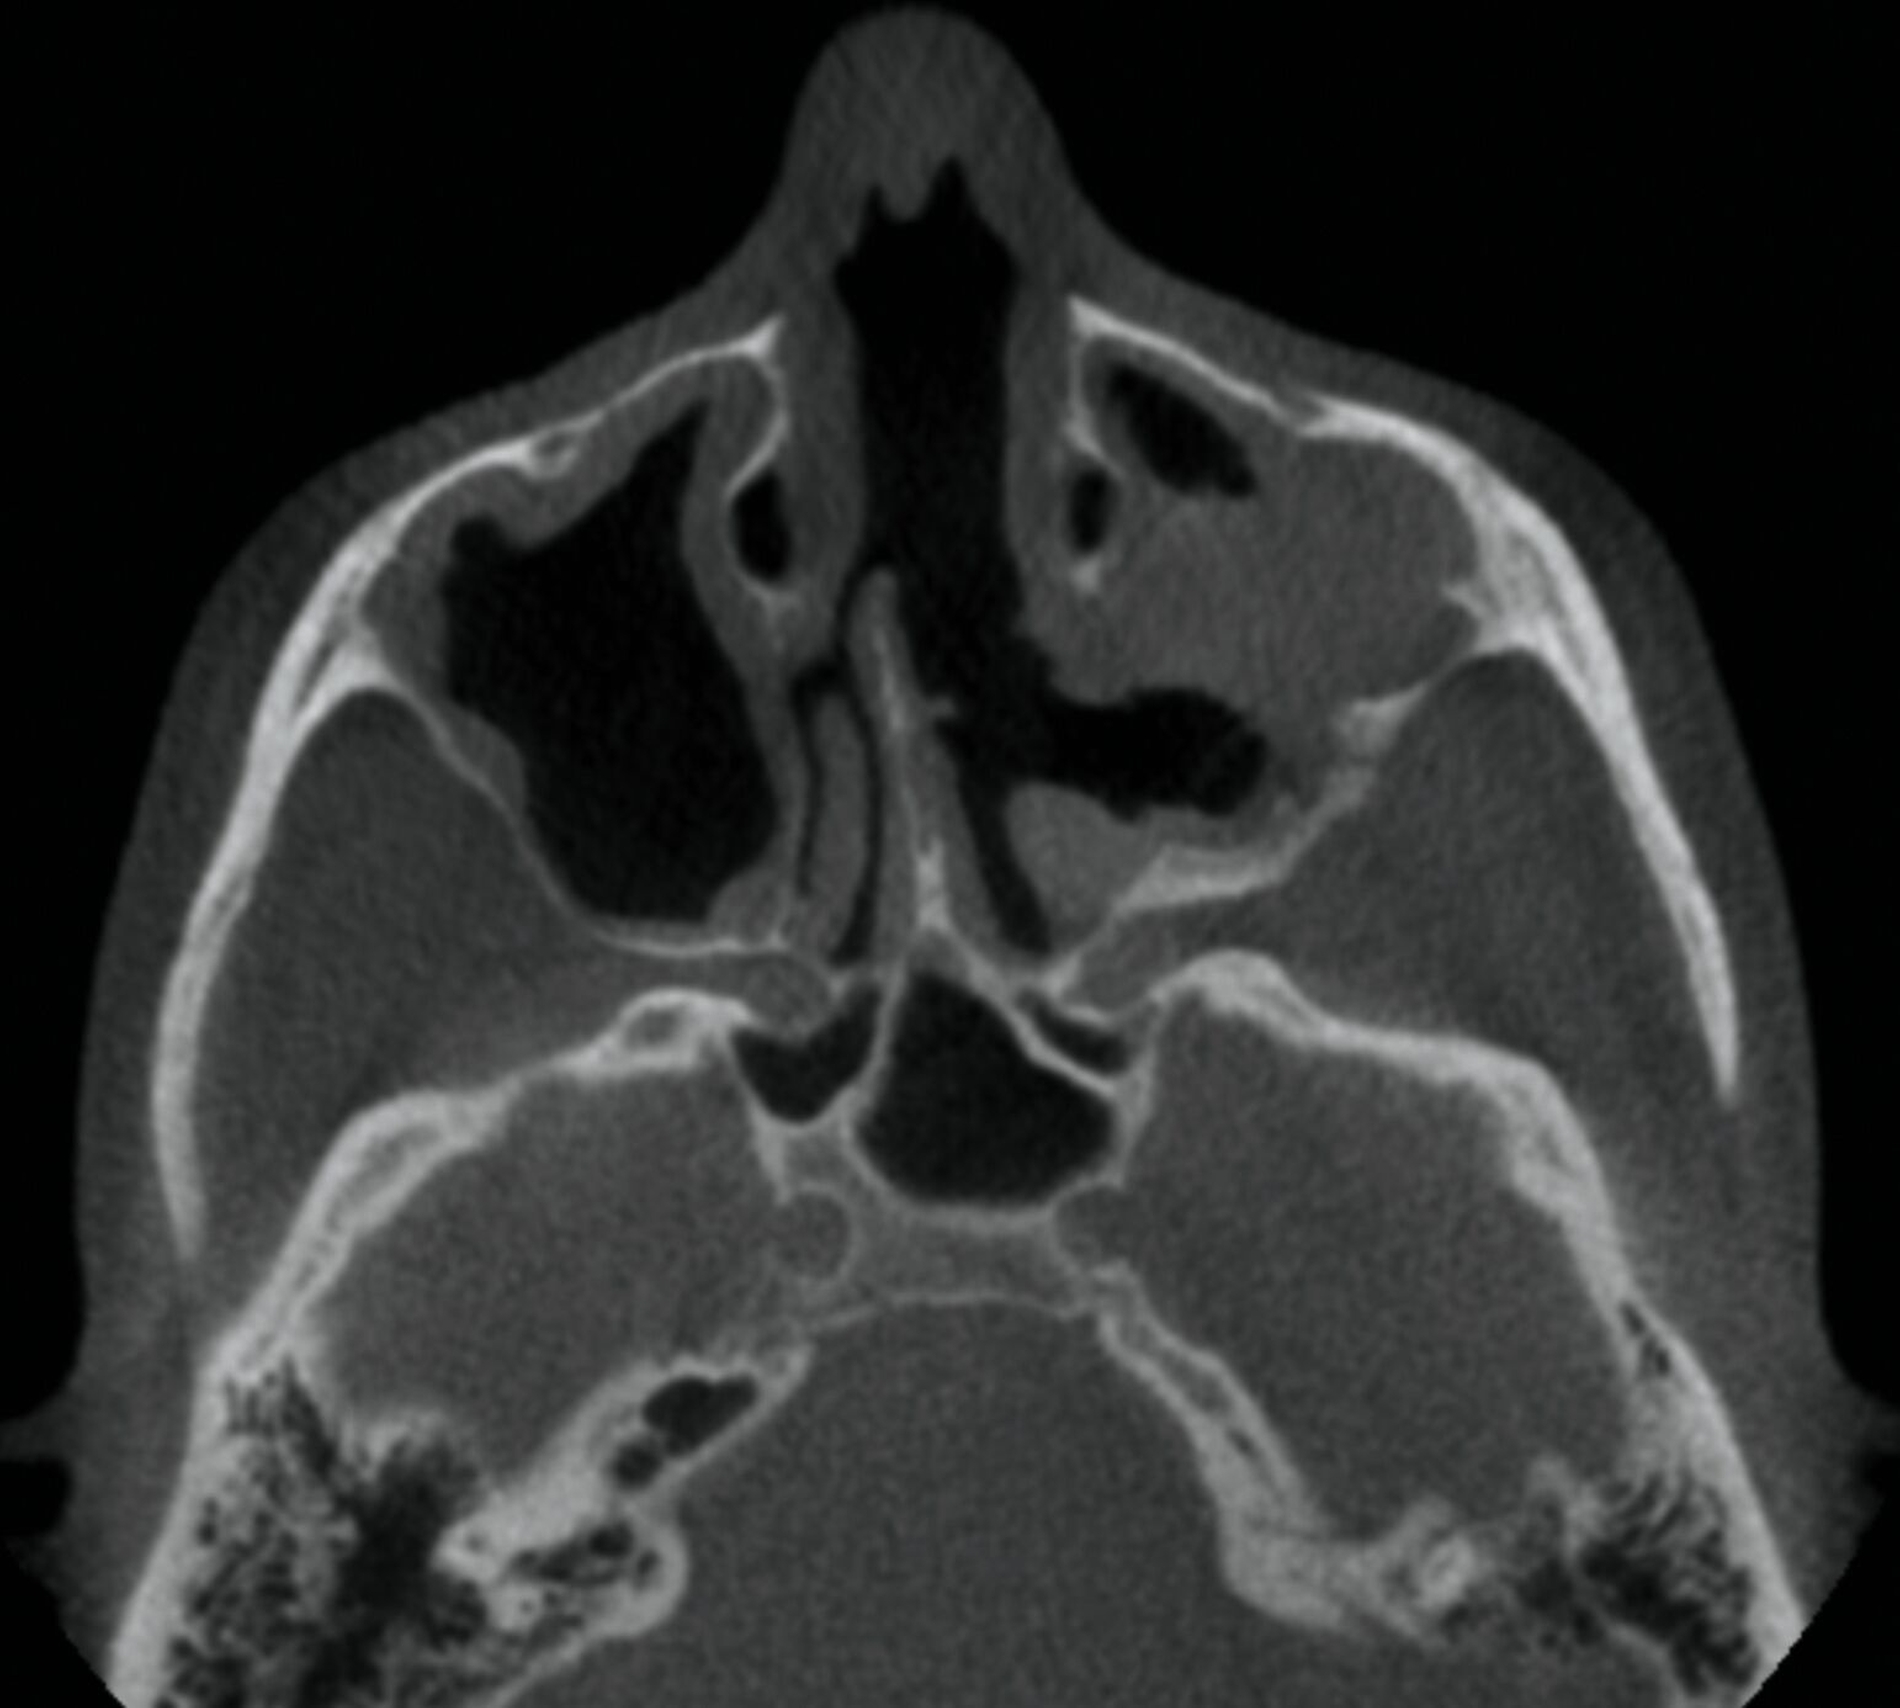

Im Verlauf stellte sich die Patientin trotz stringent eingehaltener Medikation mit erneut verstärkten Schmerzepisoden vor. Die Patientin assoziierte dies mit im Bereich der Kiefer – infolge einer im Vorfeld erfolgten Operation – vorhandenem Osteosynthesematerial zur Re-Fixierung des Kieferhöhlendeckels alio loco. Dies war von eitrigem Ausfluss aus der linken Nase begleitet. In der erweiterten Bildgebung mittels Magnetresonanztomografie zeigte die Patientin eine diffuse Kontrastmittelanhebung des Nervus infraorbitalis bildmorphologisch einer Neuritis entsprechend sowie eine diffuse Kontrastmittelanhebung des kranio-lateralen Kieferhöhlenknochens, teils mit Destruktion der kortikalen Strukturen, was den Verdacht einer Osteomyelitis nahelegte (Abbildung 4). Im zusätzlich angefertigten DVT konnte der Verdacht auf basale Aufhellung des linken Kieferhöhlenbodens bestätigt werden (Abbildung 5). Um eine definitive antimikrobielle Therapie und Diagnosesicherung zu ermöglichen, wurde die Entscheidung zur endoskopischen Probeentnahme gestellt.

Intraoperativ zeigte sich eine reizlose intakte Kieferhöhlenvorderwand mit Osteosyntheseschrauben ohne Anhalt für Lockerung oder Superinfektion (Abbildung 6). Die Schrauben wurden komplikationslos vollständig entfernt; die anteriore Kieferhöhlenwand zeigte sich als gut verheilt (Abbildung 7). Mittels transnasaler Endoskopie wurde über den vorhandenen Infundibulotomiedefekt eine mikrobiologische und histopathologische Probe entnommen. Klinisch zeigte sich eine Polyposa und gräulich-brauner Detritus.